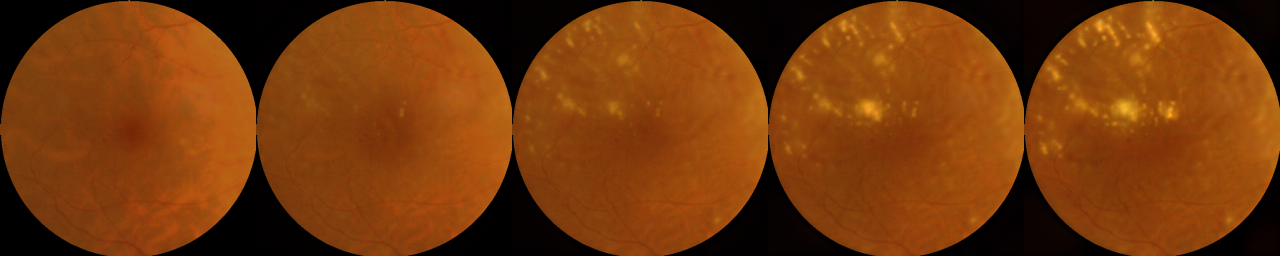

Figs. 7 and 8 presents additional examples of transformations generated by the CycleGAN’s and models respectively.

Physical interpretation. The lightening of the fovea can be shown to have a direct physical interpretation. The foveal dip [24] exists on the retinal surface around the fovea where most of the visual acuity exists. DME is caused by a swelling of this region and hence affects human vision. We believe the model is able to exploit the minute differences in reflection of light on the retinal surface near fovea to determine whether the person has DME or not. This needs to be calibrated rather precisely, which can be expected from a machine learned model on thousands of images but not humans. We believe this is also the reason why retinal specialists have been unable to capture such features. On the whole, the interpretation that the change in foveal dip causes the light to reflect differently to explain “why” the phenomenon occurs needs to be validated more extensively with paired OCT and fundus images.